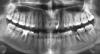

1) Нужно ли удалять 8ки, если они, как мне кажеться непроблемные, выросли ровно, не болят и не мешают?? Единственное, что на нижних появились маленькие дырочки, которые я и пришла заделать, а мне говорят удалять все напрочь, тк они все равно не нужны.

Прилагаю старый снимок (там 6ки нижней с восполением уже нет, не смотрите), новый сделаю в среду, дабы узнать как зажило на месте той 6ки.

Но на нем главное 8ки все видны!

1) По снимку показаний к удалению нет, но они могут быть, мы просто этого виртуально не можем увидеть.